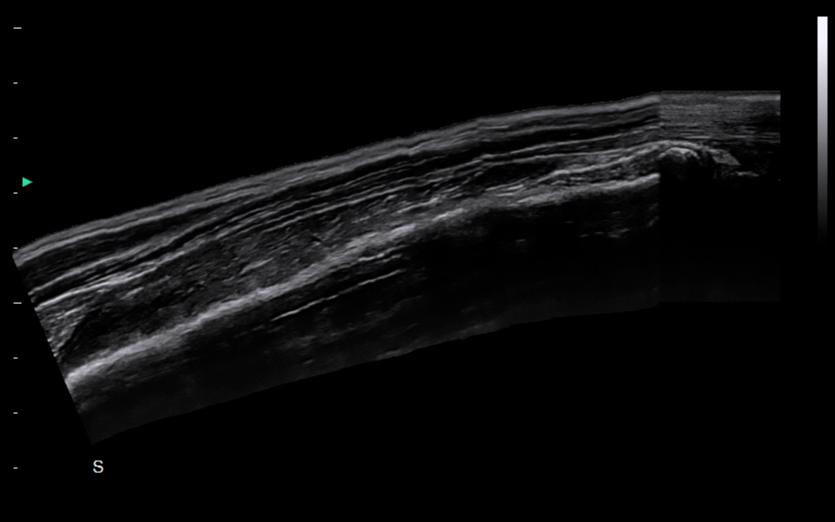

Panoscope displays image information for extensive tissue, offering abundant information of the relationship between the lesion and surrounding tissues.